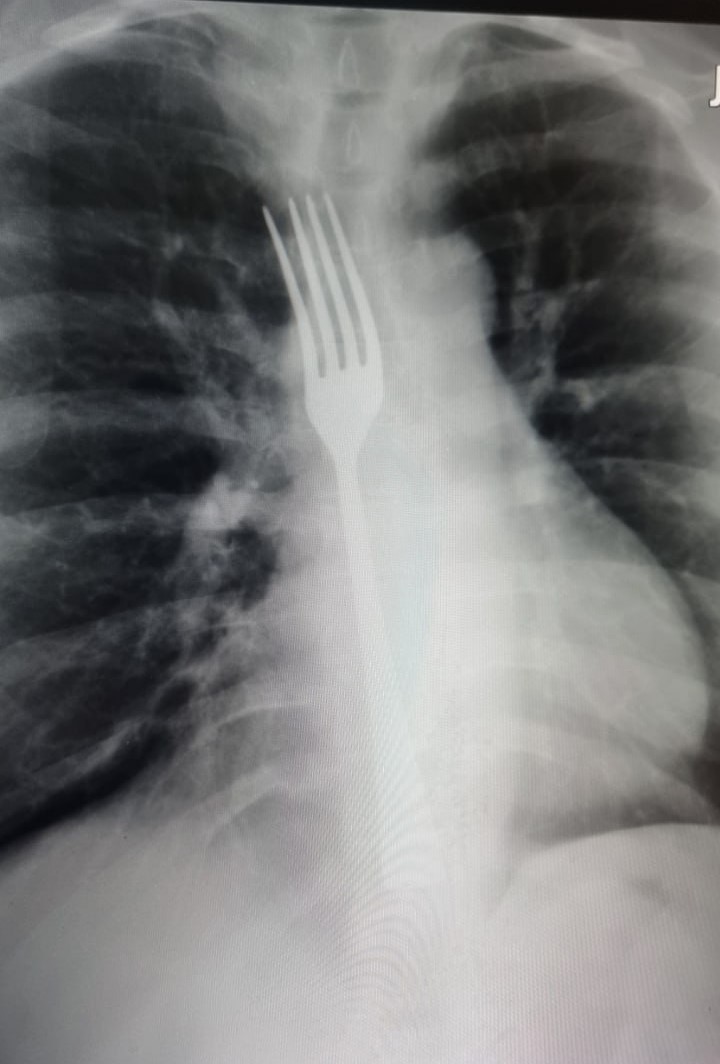

Необычный случай произошел в Витебской областной клинической больнице. Пациентка столкнулась с распространенной проблемой — «встал желудок». В попытке вызвать рвоту в домашних условиях она использовала черенок от вилки, но та застряла в пищеводе. Об этом рассказали в телеграм-канале "Витебская областная клиническая больница".

Пациентку срочно доставили в больницу и прооперировали. Благодаря профессионализму врачей удалось избежать серьезных осложнений. Во время операции инородный предмет извлекли, а повреждений пищевода удалось избежать.